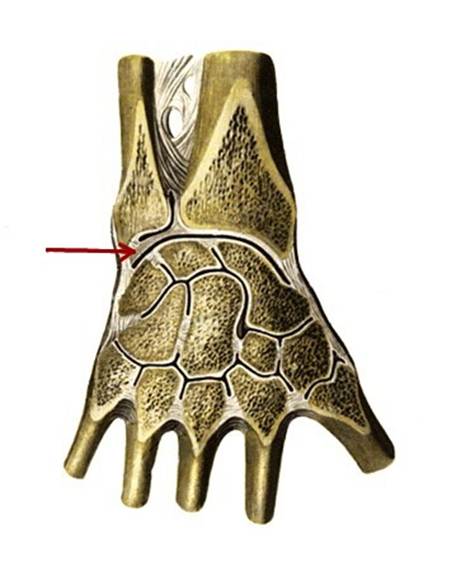

S: Стрелка указывает на art. capri